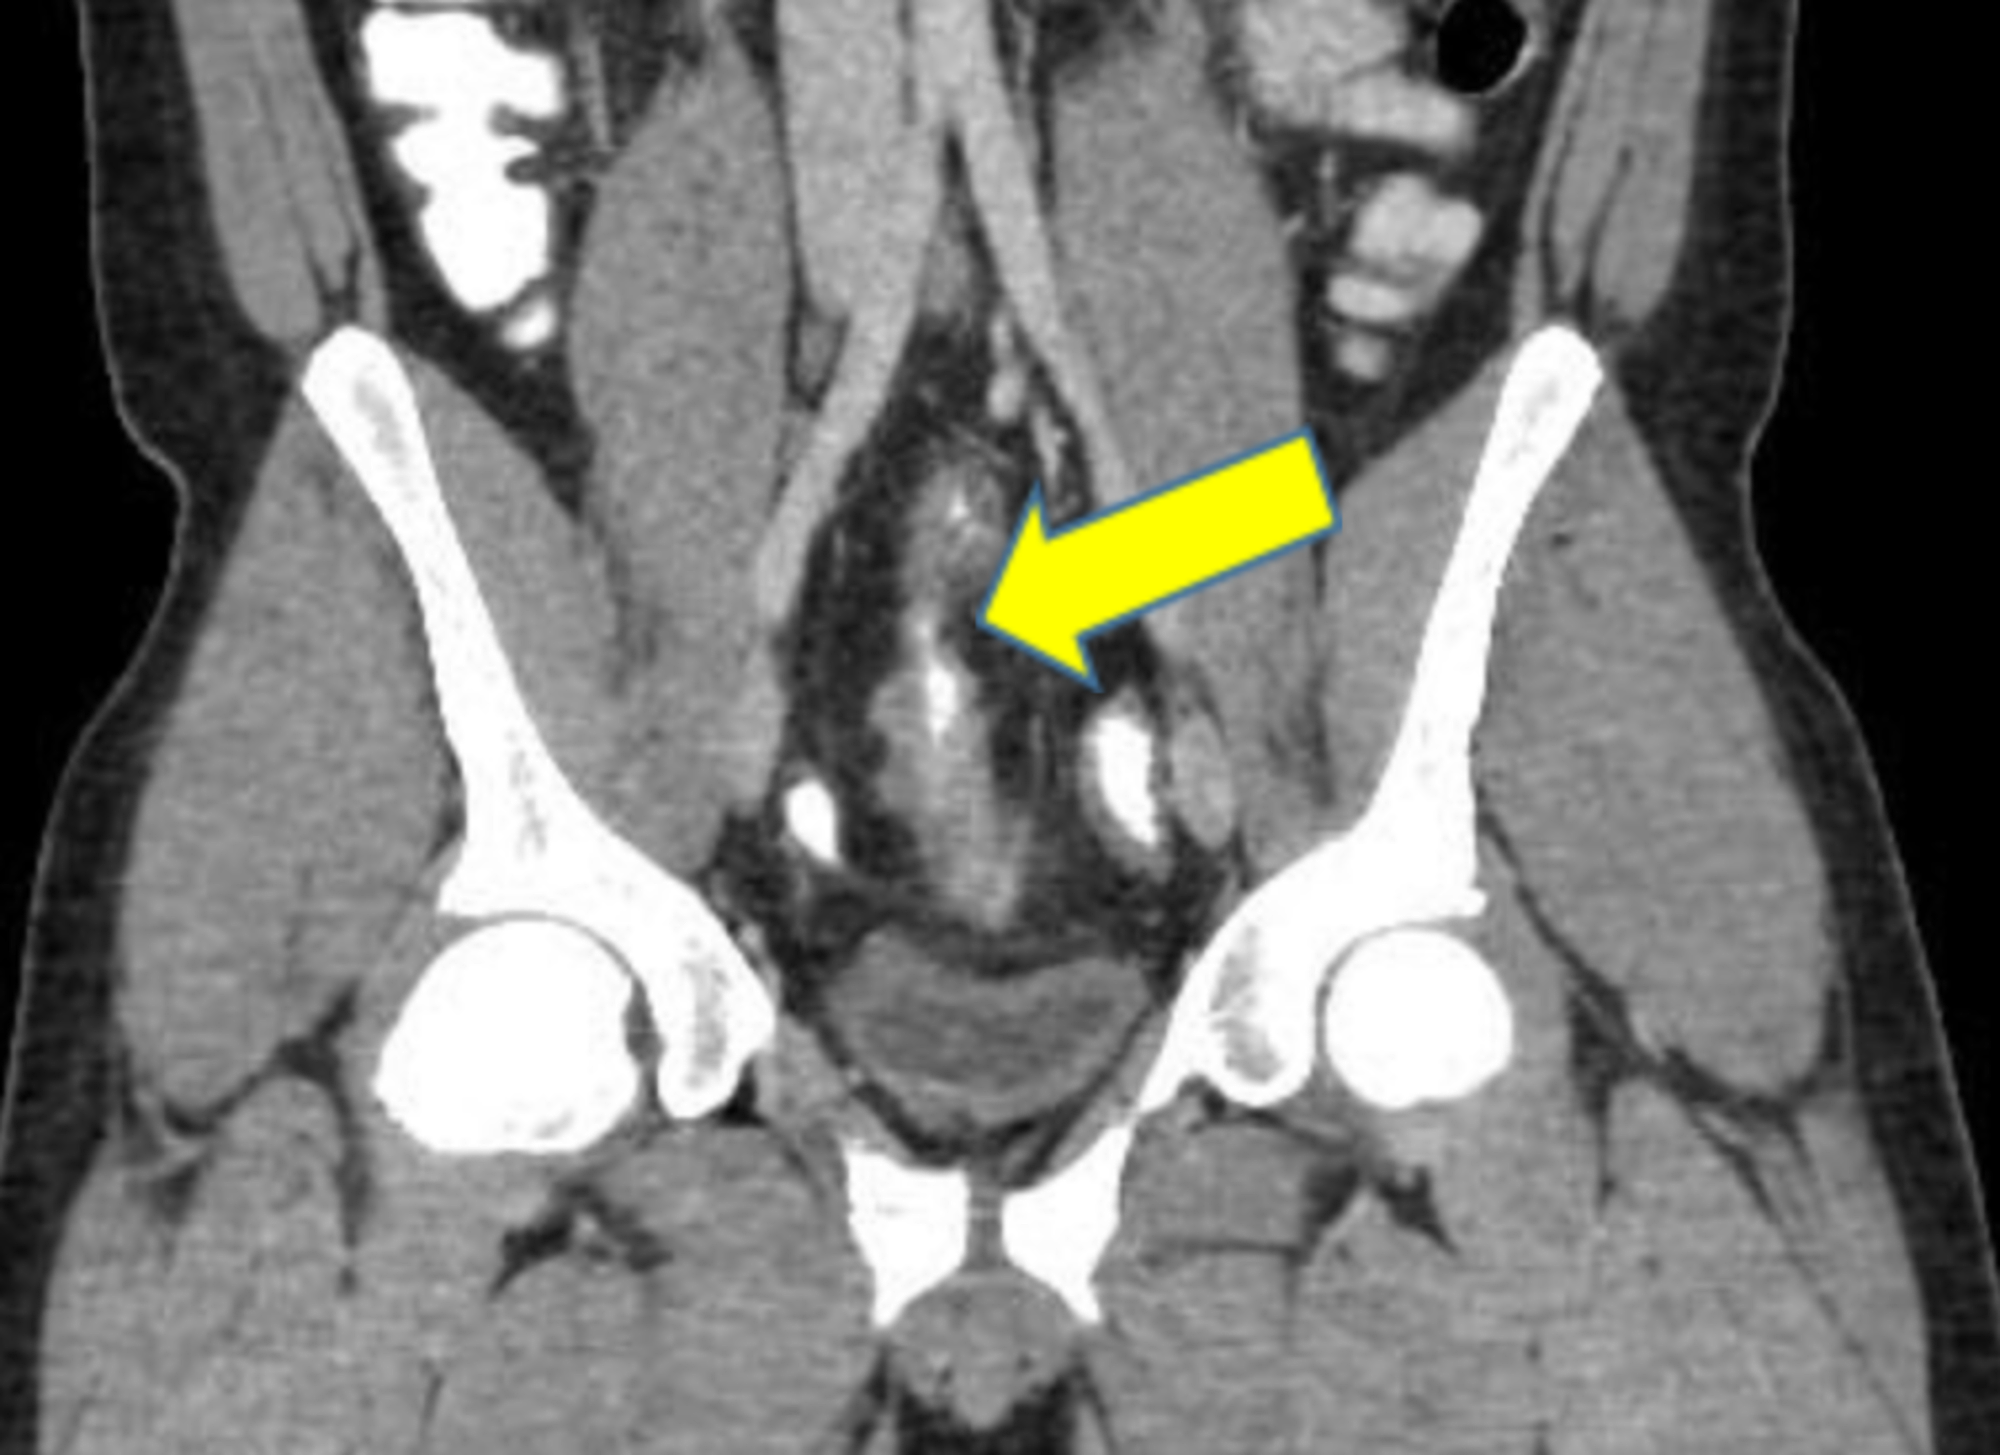

Urinary complications in Crohn’s disease and ulcerative colitis

(PDF) Crohn’s Disease and Urinary Manifestations A Crohn’s Intestinal Crohn's Disease Urine People diagnosed with crohn’s disease have a higher risk of developing kidney stones in the urinary tract than those without crohn’s, including those with ulcerative colitis. In people with crohn’s disease, hydronephrosis often occurs in the right kidney, close to the terminal ileum. Cystitis was the most common. Increased urination is one possible symptom of. Inflammatory bowel disease (ibd) is. Crohn's Disease Urine.

Cureus Recurrent Urinary Tract Infection in a Patient With Crohn's Disease Urine People diagnosed with crohn’s disease have a higher risk of developing kidney stones in the urinary tract than those without crohn’s, including those with ulcerative colitis. Ulcerative colitis (uc) and crohn disease (cd). Increased urination is one possible symptom of. Fistulizing crohn’s disease is caused by inflammation that results in the formation of a fistula —an abnormal channel between the.. Crohn's Disease Urine.

Crohn's disease. Contrastenhanced CT scan shows distal ileal loops Crohn's Disease Urine Ulcerative colitis (uc) and crohn disease (cd). People with ulcerative colitis are more likely to develop kidney stones — hard deposits of salts and minerals in the kidneys. Increased urination is one possible symptom of. Inflammatory bowel disease (ibd) is comprised of two major disorders: Cystitis was the most common. Crohn’s disease is a lifelong condition that causes inflammation in. Crohn's Disease Urine.